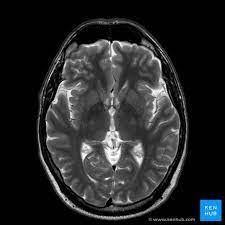

In his quest for answers, Anil consulted multiple doctors, underwent various tests, and tried several medications—yet the headache persisted, and so did his anxiety. It was during a routine visit to his neurologist, Dr. Meera Patel, that Anil first heard about advanced brain MRI technology. Dr. Meera explained that this cutting-edge diagnostic tool could provide a comprehensive view of his brain, potentially uncovering the root cause of his headaches.

As Dr. Meera elaborated on the benefits of the MRI, Anil felt a glimmer of hope. He learned that this non-invasive procedure could detect abnormalities in the brain with unparalleled accuracy, providing crucial insights into his condition. The idea of finally understanding the cause of his headaches—and, more importantly, ruling out serious conditions—brought him a sense of relief.

On the day of the MRI, Anil's heart raced with anticipation. The state-of-the-art facility, equipped with the latest MRI technology, stood as a testament to the advancements in healthcare. As the machine hummed to life, Anil closed his eyes, envisioning a future free from the constant fear and uncertainty that had plagued him.

After the procedure, Dr. Meera sat with Anil and his family, explaining the results in detail. The MRI had revealed a minor vascular issue that was treatable with medication and lifestyle changes. Anil's relief was palpable. For the first time in months, he felt a weight lift off his shoulders. The advanced brain MRI had not only provided answers but had also restored his confidence in his health and future.